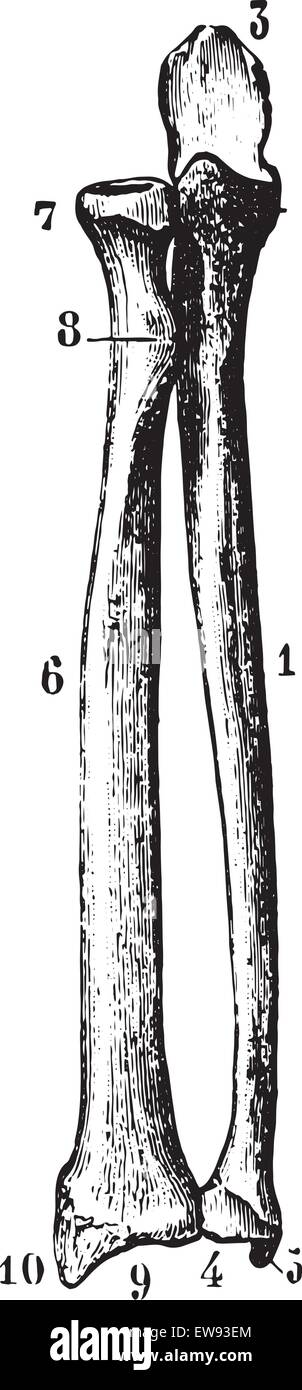

Radius and ulna (bones of the forearm) seen by their front face, vintage engraved illustration. Usual Medicine Dictionary by Dr Stock Vectorhttps://www.alamy.com/image-license-details/?v=1https://www.alamy.com/stock-photo-radius-and-ulna-bones-of-the-forearm-seen-by-their-front-face-vintage-84420011.html

Radius and ulna (bones of the forearm) seen by their front face, vintage engraved illustration. Usual Medicine Dictionary by Dr Stock Vectorhttps://www.alamy.com/image-license-details/?v=1https://www.alamy.com/stock-photo-radius-and-ulna-bones-of-the-forearm-seen-by-their-front-face-vintage-84420011.htmlRFEW9JGB–Radius and ulna (bones of the forearm) seen by their front face, vintage engraved illustration. Usual Medicine Dictionary by Dr

Radius and ulna (bones of the forearm) seen by their front face, vintage engraved illustration. Usual Medicine Dictionary by Dr Stock Vectorhttps://www.alamy.com/image-license-details/?v=1https://www.alamy.com/stock-photo-radius-and-ulna-bones-of-the-forearm-seen-by-their-front-face-vintage-84408204.html

Radius and ulna (bones of the forearm) seen by their front face, vintage engraved illustration. Usual Medicine Dictionary by Dr Stock Vectorhttps://www.alamy.com/image-license-details/?v=1https://www.alamy.com/stock-photo-radius-and-ulna-bones-of-the-forearm-seen-by-their-front-face-vintage-84408204.htmlRFEW93EM–Radius and ulna (bones of the forearm) seen by their front face, vintage engraved illustration. Usual Medicine Dictionary by Dr